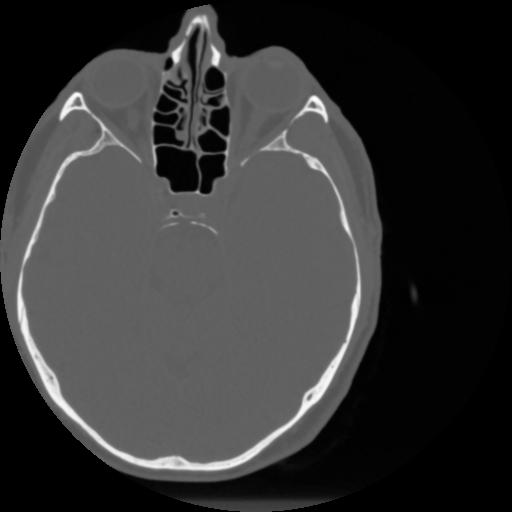

4 CEREBRO,,Vol,0.5,CEREBRO,,